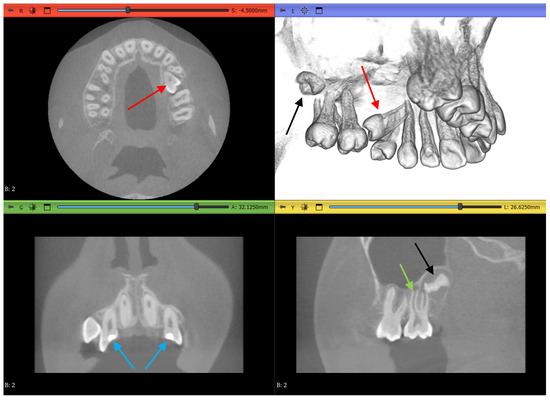

3.5. Results of Dataset 3